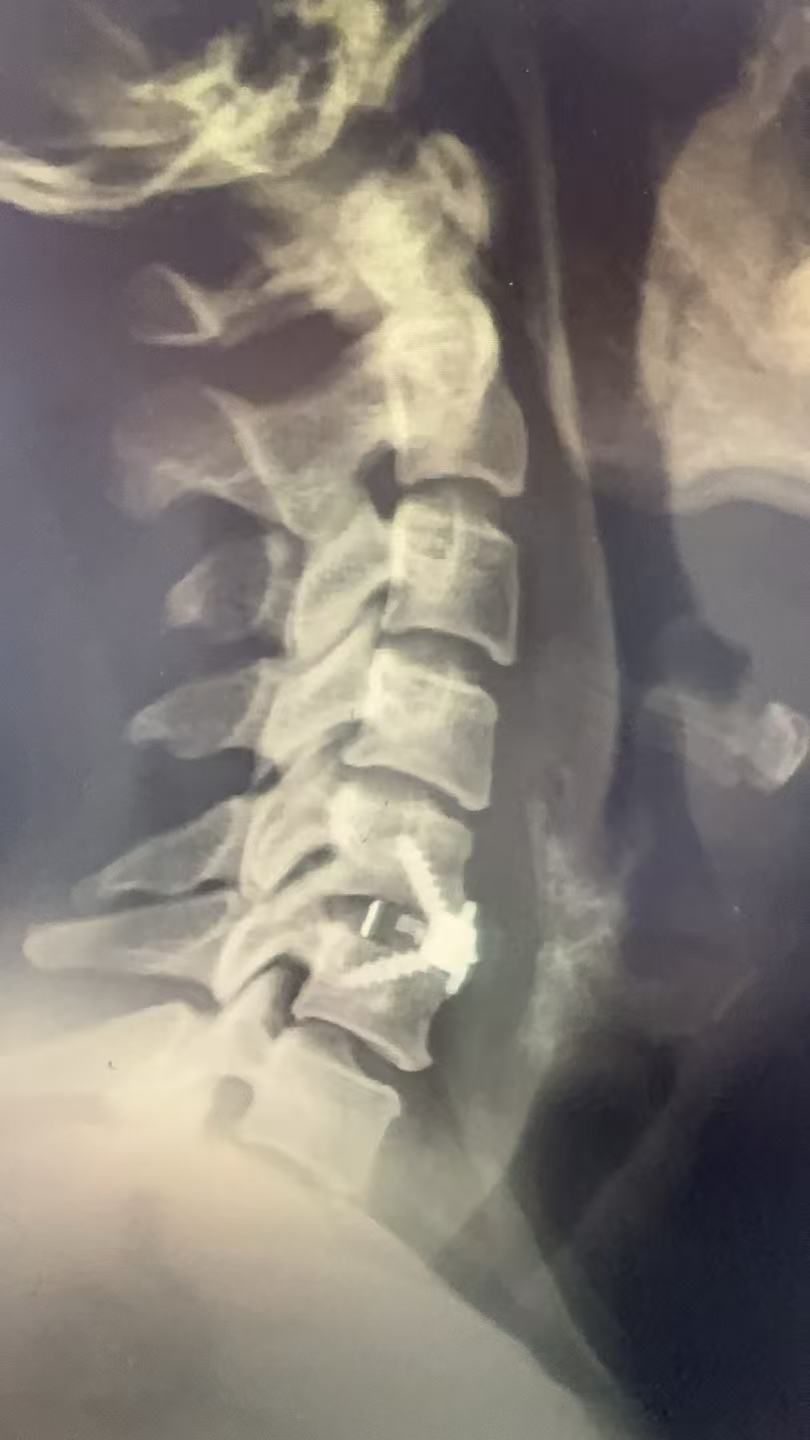

经我院脊柱外科团队详细检查,磁共振显示其颈5/6节段椎间盘突出,已压迫脊髓及神经根,保守治疗效果不明显。为从根本上解除神经压迫,手术成为合适的选择。

经过充分的术前评估与方案讨论,在南方医科大学第三附属医院(以下简称“南医三院”)派驻骨科专家、东凤人民医院副院长闫慧博(挂职)的带领下,我院骨科团队为陈女士实施颈椎前路椎间盘摘除+椎体融合术

手术过程顺利,手术切口2.5cm,术中出血量仅10ml,手术时长1小时。

(术后图)

术后麻醉清醒后,陈女士即感颈部疼痛和手麻症状显著缓解。术后一天可在颈托保护下自主活动。